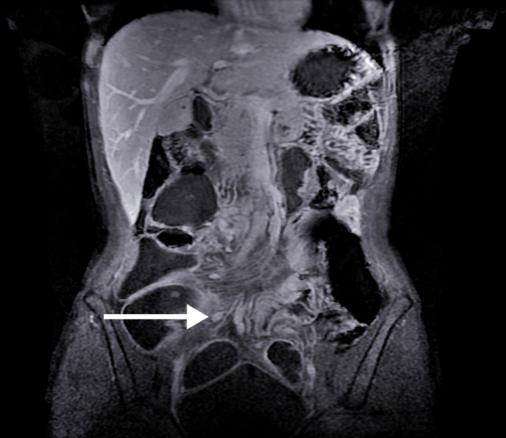

IRM. Adénopathies mésentériques chez une malade ayant une maladie de Crohn de l'iléon.